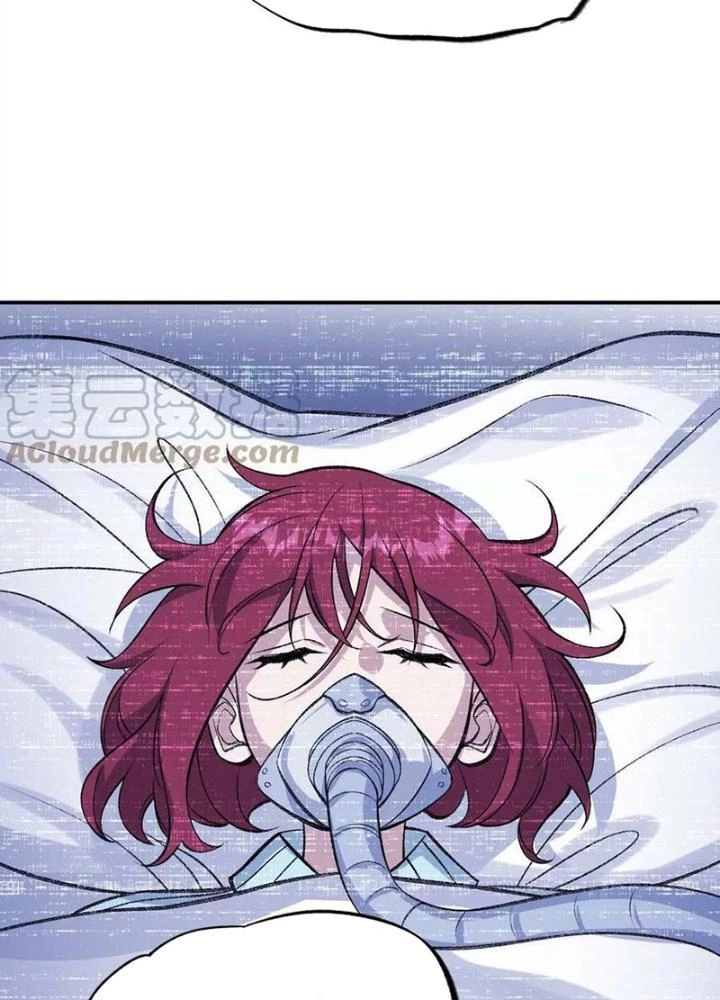

Thời Kỳ Tận Thế - Chapter 133